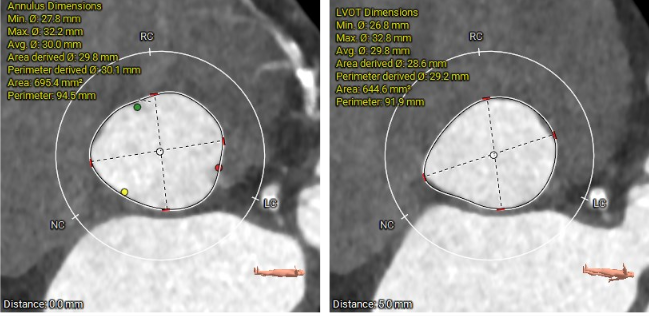

三叶三窦式主动脉瓣

瓣环周长94.5mm,平均周长径30.1mm;

SOV瓦式窦:32.6mm *35.4mm*36.9mm ;

LVOT周长91.9mm,平均周长径 29.2mm。

STJ平面周长115.2mm;

升主动脉最大直径47.6mm;

瓣叶重度钙化合并增厚,钙化分布不均,主要集中于左冠窦内。

HU953 积分862mm²。

左冠高度14.7mm 右冠高度15.1mm;

瓣口对应瓣叶稍冗长,术中须注意冠脉风险。

心脏水平夹角67°,横位心;

左室腔内径尚可,心室壁增厚明显。